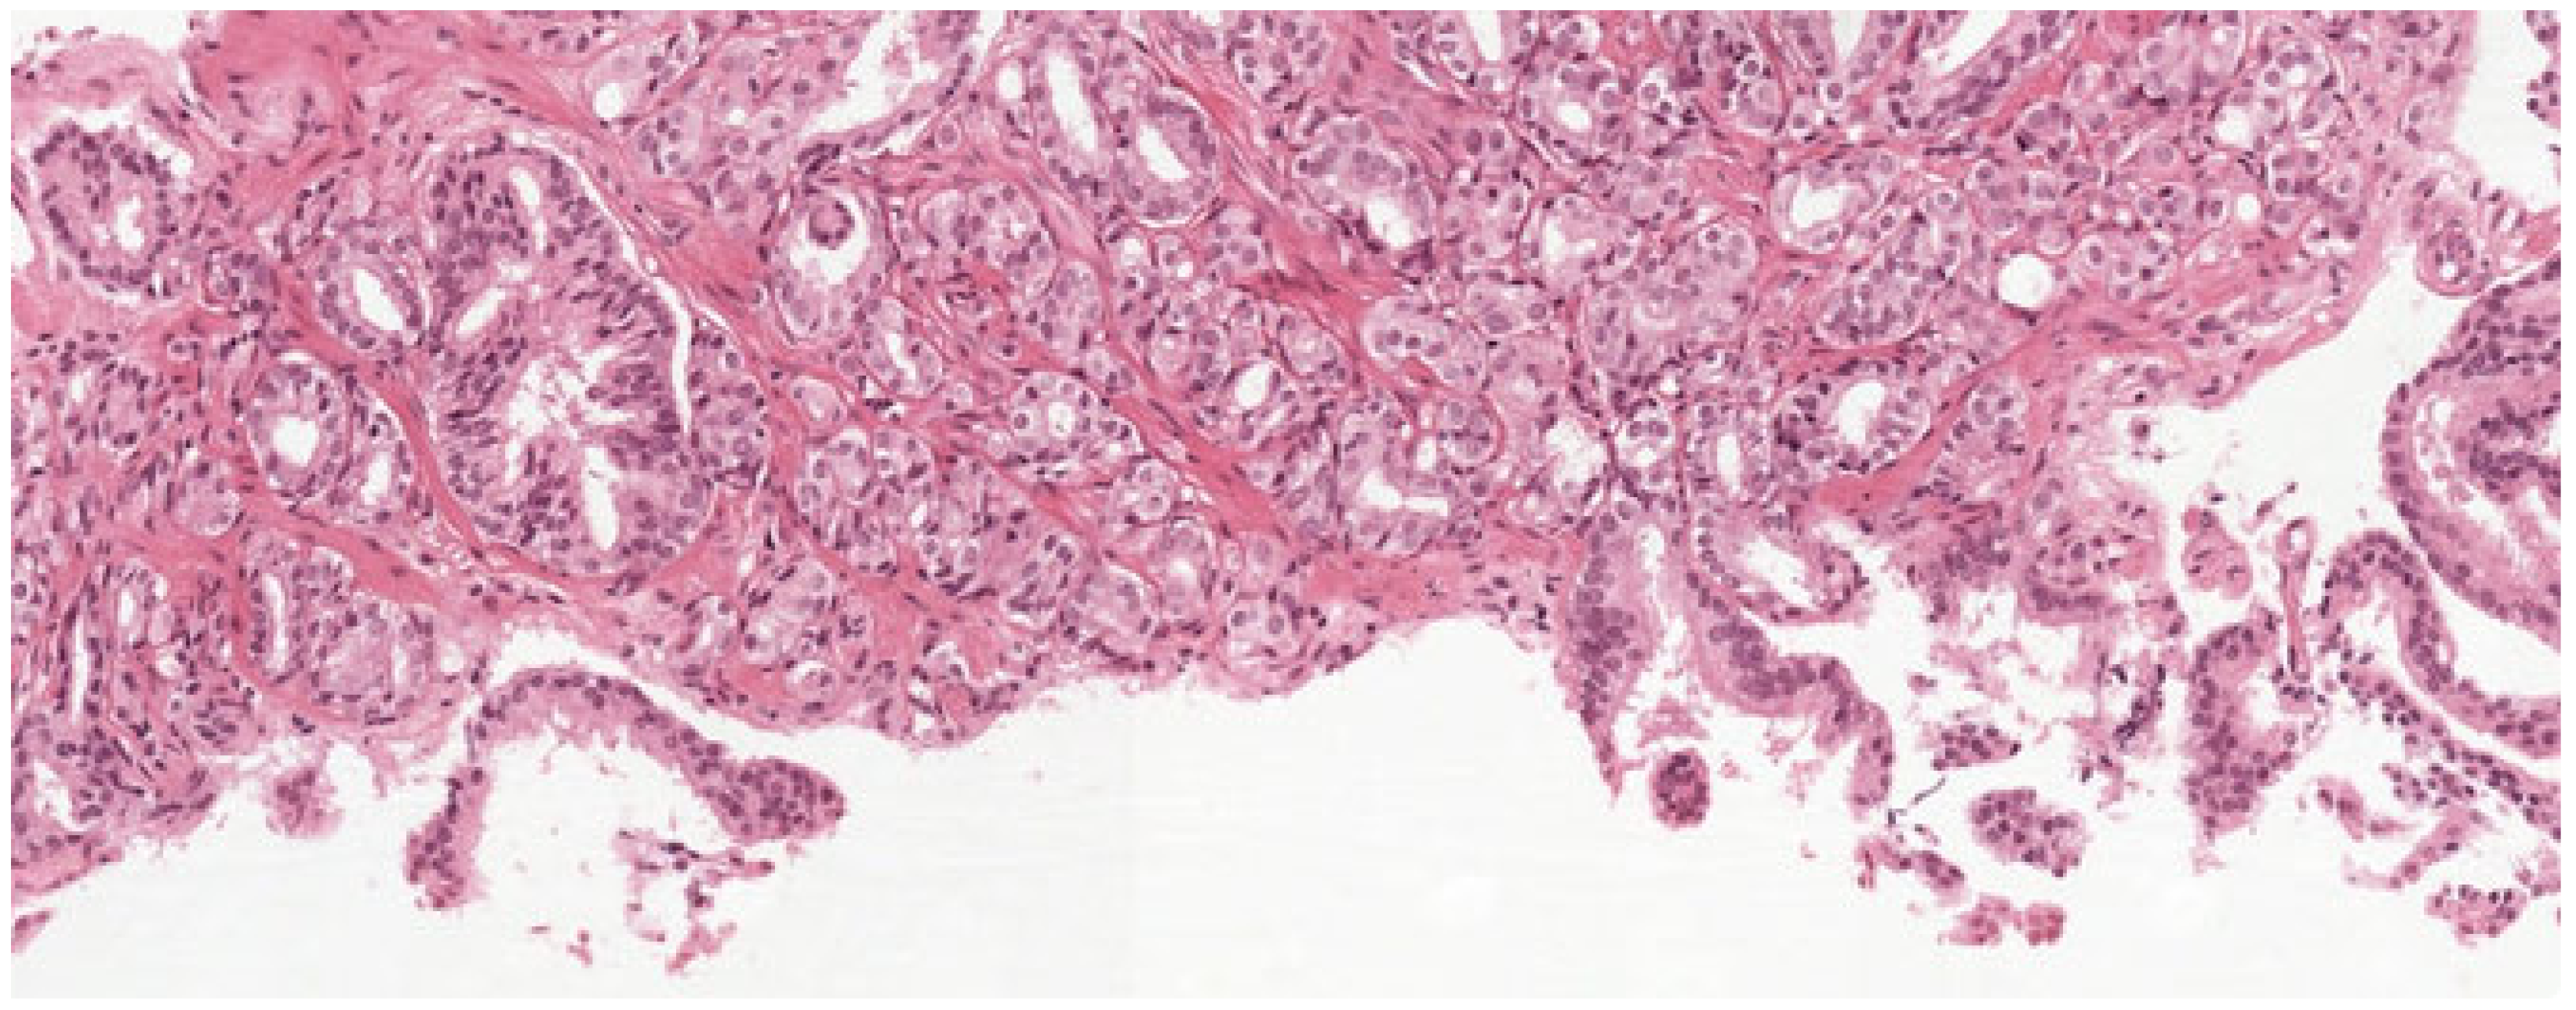

| Digital Pathology Dataset [116] | Whole Slide Images (H&E-stained); Tan Tock Seng Hospital | Histopathology | 99 WSIs | Gland segmentation and classification |

| Peso Dataset [120] | WSIs with annotations; Radboud University Medical Centre | Histopathology | 102 WSIs | Cancer detection and classification |

| Gleason Challenge [122] | Tissue Microarrays (TMAs); Vancouver Prostate Center | Histopathology | 244 training + 87 test TMAs | Gleason grading classification |

| PANDA Challenge [127] | Largest publicly available prostate WSIs; Radboud & Karolinska | Histopathology | ∼11,000 WSIs | AI development for Gleason grading |